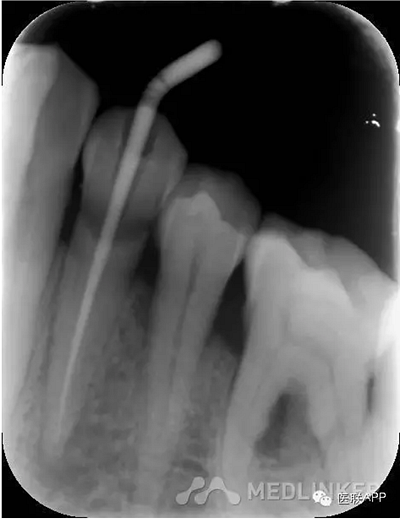

初診:頰側去腐,合面常規(guī)開髓揭頂,拔髓,電測根長WL=22mm,EDTA下手擴+機擴+protaper根備至F2,CR反復沖洗,干燥,Vitapex根充,ZOE暫封,約日復診。